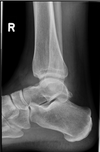

Q

error

A

internal rotation